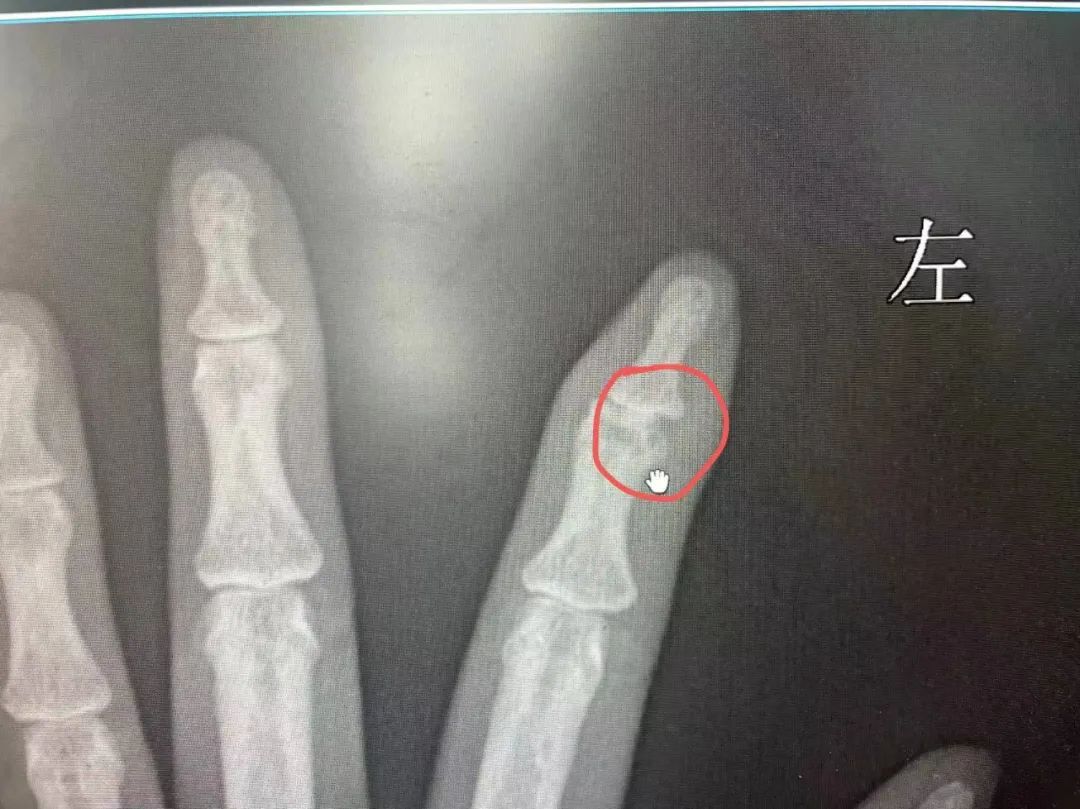

武汉女子吃顿烧烤险些失去手指

武汉一名女子吃烧烤时

竹签不慎扎入手指

用指甲剪将竹签拔出便没再管它

两个月后

受伤的手指染上了骨髓炎

险些失去手指指尖

医生介绍,像竹签、海鲜、鱼刺等物体都可能带有细菌,如果扎进人的身体里很有可能引发感染,加上反复化脓,最终会引起骨髓炎。